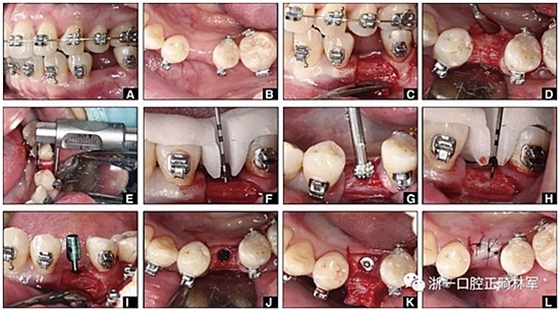

圖12.將種植體植入正畸產(chǎn)生的間隙中的步驟:A,將下頜左側第二前磨牙向遠中移動以在前磨牙之間產(chǎn)生間隙; B,種植部位的咬合面觀; C,一個水平切口和兩個垂直切口,距相鄰牙齒1.5mm的距離; D,暴露的牙槽嵴的咬合面觀; E,測量牙槽嵴的寬度約6mm; F,手術導板顯示預備冠頸部的位置距離骨牙槽嵴頂僅1毫米; G,用球鉆修整牙槽嵴; H,建立3mm從手術導板的頸部輪廓到骨嵴的距離,以實現(xiàn)必要的生物學寬度; I,引導針顯示了截骨的角度; J,3.5×10mm種植體完全置于骨內(nèi); K,一個覆蓋螺帽就位; 和L,縫合。

圖13. A,下頜右側第一磨牙區(qū)缺牙區(qū)咬合面觀; B,做1個水平的冠狀切口和2個垂直切口; C,暴露牙槽嵴; D,放置導針確保合適的就位道; E,放置3.5×10mm種植體; F,有暴露的種植體界面(粗糙表面); G,連接愈合基臺,并將骨粉(凍干的同種異體骨和Bio-Oss)置于頰側以覆蓋暴露的種植體表面; H,縫合。

治療過程

完全固定的Damon Q設備(加利福尼亞州Glendora的Ormco)與制造商指定的弓絲和附件一起使用。下頜弓,一開始放入0.014英寸的鎳鈦弓絲,5個月后放入0.014×0.025英寸的鎳鈦弓絲。舌側扣和鏈圈放置在下頜尖牙和第二前磨牙上以控制扭轉。在治療的第7個月,將下頜弓絲換成0.017× 0.025英寸的β鈦絲。另一個舌側扣和鏈圈放置在下頜左側第三磨牙上以提供近中牽引力(圖9)。在16個月的治療結束時,所有的扭轉都得到了矯正,缺牙間隙縮小到8 mm(圖8),但由于頰側骨板的嚴重吸收,牙槽嵴的寬度仍然很窄(約3 mm)(圖9)。通過正畸移動下頜左側第二前磨牙,在前磨牙之間產(chǎn)生一個種植部位。在第一和第二前磨牙之間的弓絲上放置一個推簧,并將舌側扣和鏈圈放置在第一前磨牙和第三磨牙之間(圖9),在頰側和舌側施加力。施力均為輕力,每個表面上約2盎司(28.3 cN)以控制牙根側面的吸收。

圖10.經(jīng)過7個月后,以每月1毫米的速度牽引下頜左側第二前磨牙,正畸產(chǎn)生的種植部位長約7毫米。通過使用固定矯治器保持間隙6個月。根尖X線片顯示第二前磨僅有少量牙根遠中面吸收。